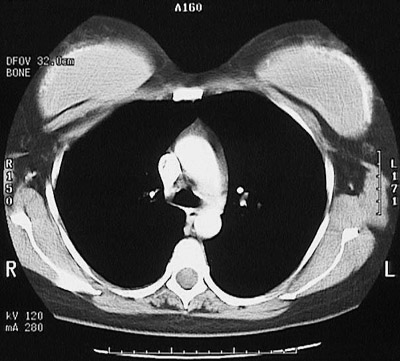

This chest CT scan reveal breast implants on the

right

and on the

left

. These implants have resulted in the formation of a fibrous capsule that has

partially calcified

.